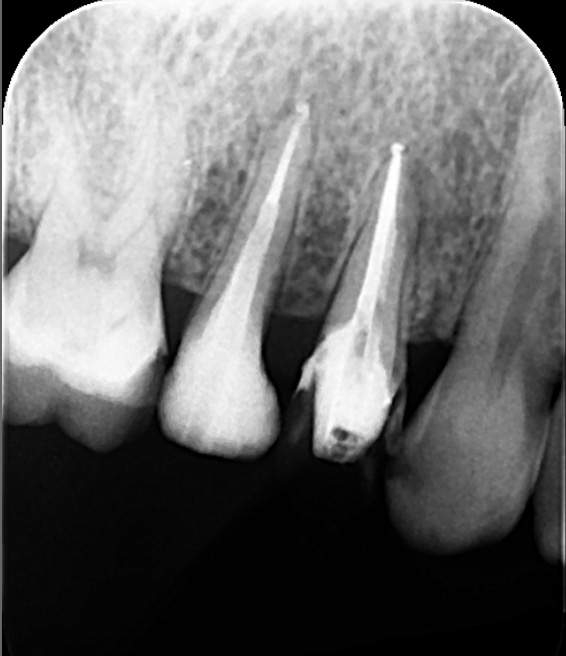

根管治療前に撮影したCT画像です。歯根の中央くらいまでしか根管充填されていませんでした。

根管の石灰化を除去し根の先まで根管充填を行いました。